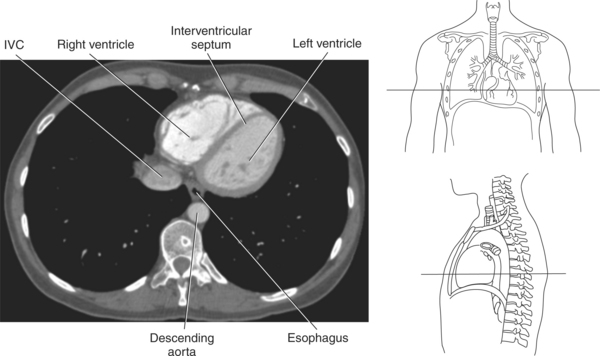

The heart is a hollow, four-chambered muscular organ located within the middle mediastinum. It is approximately the size of a large clenched fist and is situated obliquely in the chest with one third of its mass lying to the right of the median plane and two thirds to the left. The heart can be described as being roughly trapezoid shaped (Figure 6.33). The superficial relationships of the heart include the base, apex, three surfaces (sternocostal, diaphragmatic, pulmonary), and four borders (right, inferior, left, and superior). The broad base (posterior aspect) is the most superior and posterior portion of the heart. It is formed by both atria, primarily the left atrium, and gives rise to the great vessels. The apex is formed by the left ventricle and points inferiorly, anteriorly, and to the left. It is located at the level of the fifth intercostal space, just medial to the midclavicular line. The sternocostal (anterior surface) is formed primarily by the right atrium and right ventricle with a small contribution from the left ventricle. The diaphragmatic (inferior surface) rests on the central tendon of the diaphragm and is formed by both ventricles and a small portion of the right atrium. The pulmonary (left surface) is formed mainly by the left ventricle and fills the cardiac notch of the left lung. The borders of the heart represent the external surfaces of the cardiovascular silhouette in radiographic profile. The borders include the right border, formed by the right atrium and located between the superior and inferior venae cavae; the left border, formed by the apex of the heart or the left ventricle; the superior border, formed by the right and left atria; and the inferior border, which is formed primarily by the right ventricle with a small contribution from the left ventricle (Figures 6.33 through 6.35).

The walls of the heart consist of three layers: (1) epicardium, the thin outer layer that is in contact with the pericardium; (2) myocardium, the thick middle layer consisting of strong cardiac muscle; and (3) endocardium, the thin, endothelial layer lining the inner surface. The endothelial layer also lines the valves of the heart and is continuous with the inner lining of the blood vessels. The heart is divided into four chambers: the right and left atria and the right and left ventricles. The two superior collecting chambers called atria are divided by the interatrial septum. During embryonic development an oval opening exists within the interatrial septum called the foramen ovale. This opening allows blood flow between the right and left atria during fetal lung development. At birth, the foramen ovale closes, leaving a small depression in the septal wall called the fossa ovalis in the adult heart. The two inferior pumping chambers called ventricles are divided by the interventricular septum (Figure 6.39).

The right atrium forms the right border of the heart and receives deoxygenated blood from the body via the superior and inferior venae cavae and from the coronary sinus and cardiac veins that drain the myocardium. A small muscular embryonic appendage, the right auricle, projects upward and toward the left from the right atrium, covering the root of the aorta (Figure 6.40). The right ventricle lies on the diaphragm and comprises the largest portion of the anterior surface of the heart. It receives deoxygenated blood from the right atrium and forces it into the pulmonary trunk for conveyance to the lungs. Projecting off the inferior surface of the ventricular walls are conical-shaped projections of cardiac muscle called papillary muscles that anchor the cusps of the tricuspid valve to the right ventricle (Figure 6.39). The left atrium lies posterior to the right atrium and is the most posterior surface of the heart. It also has an embryonic appendage, the left auricle, that projects to the left of the pulmonary trunk over the superior surface of the heart. The left atrium receives oxygenated blood directly from the lungs via the four pulmonary veins (two on each side). The left ventricle forms the apex, left border, and most of the inferior surface of the heart. It receives oxygenated blood from the left atrium and pumps it into the aorta for distribution throughout the systemic circuit. The myocardium of the left ventricle is normally three times thicker than that of the right ventricle, reflecting the force necessary to pump blood to the distant sites of the systemic circulation (Figures 6.41 through 6.52). Two papillary muscles project from the ventricular walls to anchor the bicuspid valve to the ventricle (Figures 6.39 and 6.47).

Blood travels to and from the heart through the great vessels, which include the aorta, pulmonary arteries and veins, and superior and inferior venae cavae (Figures 6.54 and 6.55). The aorta is the largest artery of the body and can be divided into the ascending aorta, aortic arch, and descending aorta. The ascending aorta begins at the base of the left ventricle at the level of the sternal angle, then curves superiorly and posteriorly as the aortic arch over the root of the left lung. The top of the aortic arch is approximately at T3 (Figures 6.56 and 6.57). The arch continues as the descending aorta posterior to the left bronchus and pulmonary trunk, on the left side of the vertebral body of T4 (Figures 6.58 and 6.59). The descending aorta passes slightly anterior and to the left of the vertebral column as it descends through the thoracic and abdominal cavities (Figure 6.60). While in the thoracic cavity, the descending aorta is commonly called the thoracic aorta, and while in the abdominal cavity, it is called the abdominal aorta. The pulmonary trunk is the origin of the right and left pulmonary arteries and lies entirely within the pericardial sac. It arises from the right ventricle and ascends in front of the ascending aorta, courses posteriorly and to the left, where it bifurcates at the level of the sternal angle (T4) into the right and left pulmonary arteries (Figures 6.61 through 6.63). The pulmonary trunk is attached to the aortic arch by a fibrous cord called the ligamentum arteriosum, the remnant of an important fetal blood vessel (ductus arteriosus) that links the pulmonary and systemic circuits during fetal development (Figures 6.54 and 6.61). The right pulmonary artery courses laterally, posterior to the ascending aorta and superior vena cava, and anterior to the esophagus and right mainstem bronchus, to the hilum of the right lung. At the root of the right lung, the right pulmonary artery divides into two branches, with the lower branch supplying the middle and inferior lobes and the upper branch supplying the superior lobe (Figures 6.61 through 6.64). The left pulmonary artery, shorter and smaller than the right, is also the most superior of the pulmonary vessels. It travels horizontally, arching over the left mainstem bronchus, and enters the hilum of the left lung just superior to the left mainstem bronchus (Figures 6.61 through 6.64). Within the lungs, each pulmonary artery descends posterolateral to the main bronchus and divides into lobar and segmental arteries, continuing to branch out and to follow along with the smallest divisions of the bronchial tree (Figures 6.61 and 6.64). Located inferior to the pulmonary arteries are the four pulmonary veins, two each (superior and inferior) extending from each lung to enter the left atrium (Figures 6.54, 6.55, 6.61, and 6.64 through 6.68). They commence in a capillary network along the walls of the alveoli, where they are continuous with the capillaries of the pulmonary arteries. The venous capillaries merge to form small vessels that unite successively to eventually form a single trunk for each lobe: three for the right and two for the left lung. Frequently the trunk from the middle lobe of the right lung unites with the trunk from the upper lobe, forming just two trunks on the right side prior to entering the left atrium. The right superior pulmonary vein collects blood from the upper lobe segments of the right lung and passes anterior and inferior to the right pulmonary artery, behind the superior vena cava. The right inferior pulmonary vein receives blood from the right lower lobes of the lung and crosses behind the right atrium to the left atrium (Figures 6.61 and 6.69 through 6.71). The left superior pulmonary vein receives blood from the left upper lobe of the left lung and courses anterior and inferior to the left main bronchus as it enters the left atrium. The left inferior pulmonary vein drains the inferior lobe of the left lung and passes toward the left atrium anterior to the bronchi (Figures 6.61 and 6.72 through 6.74). The pulmonary veins course more horizontally than the pulmonary arteries and are ultimately oriented toward the left atrium. At the root of the lungs, the pulmonary veins are anterior to the pulmonary arteries, which are anterior to the bronchus. While within the lungs, the branches of the pulmonary arteries are anterior to the bronchi, which are anterior to the pulmonary veins. The superior and inferior venae cavae are the largest veins of the body. The superior vena cava is formed by the junction of the brachiocephalic veins, posterior to the right first costal cartilage, and carries blood from the thorax, upper limbs, head, and neck (Figure 6.24). As it travels inferiorly, it is located posterior and lateral to the ascending aorta before entering the upper portion of the right atrium (Figures 6.54 through 6.59). The inferior vena cava is formed by the junction of the common iliac veins in the pelvis and ascends the abdomen to the right of the abdominal aorta and anterior to the vertebral column. It passes through the caval hiatus of the diaphragm and almost immediately enters the inferior portion of the right atrium (Figures 6.75 and 6.76).